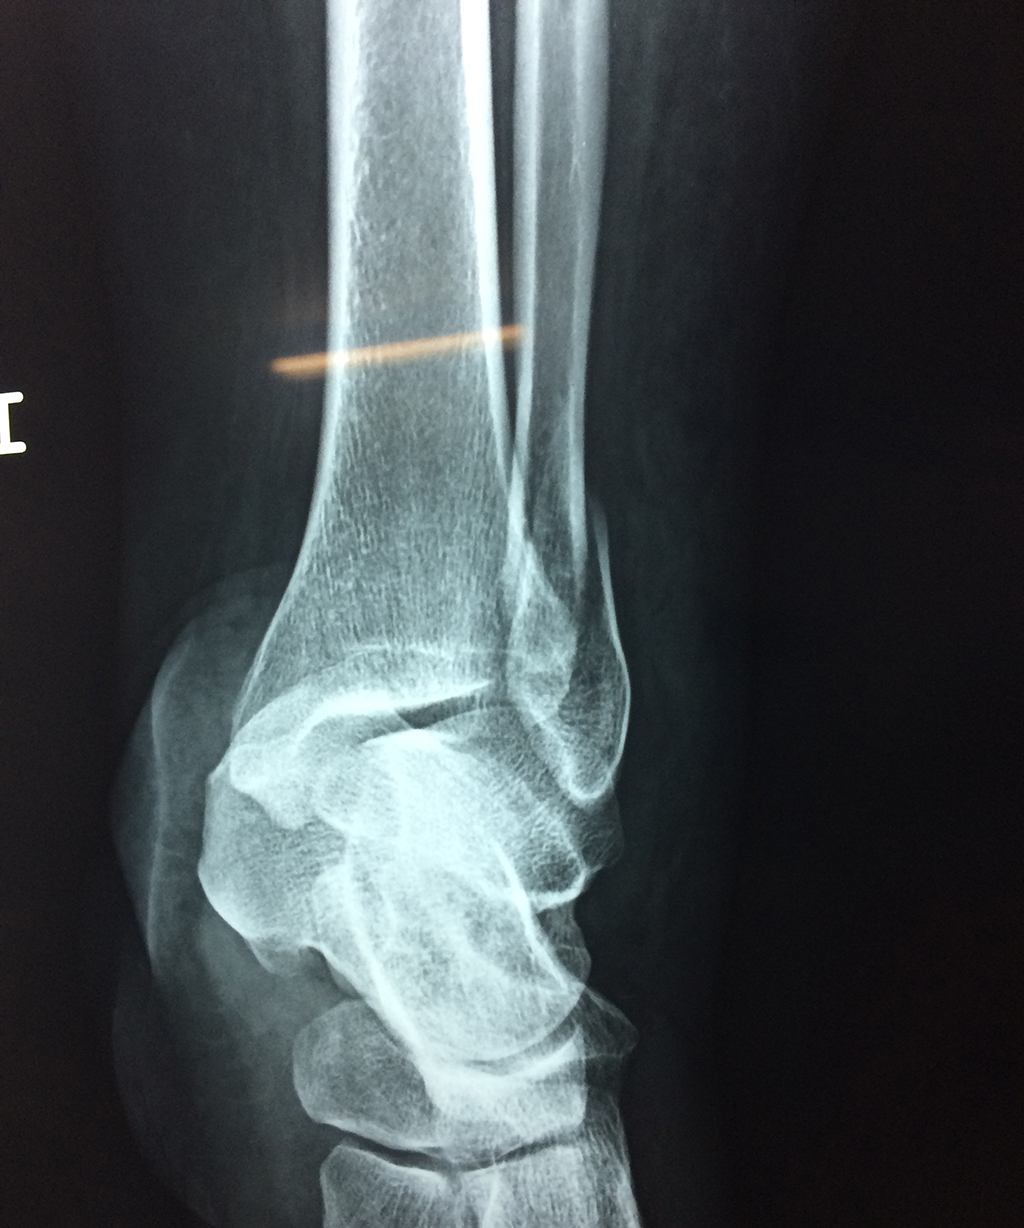

Una fractura de tobillo es la rotura de uno o más de los huesos del tobillo. Estas fracturas pueden ser:

- Parciales (el hueso está sólo parcialmente fisurado, no del todo).

- Completas (el hueso está perforado y está en 2 partes).

- Producirse en uno o ambos lados del tobillo.

Algunas fracturas de tobillo pueden requerir cirugía si:

- Los extremos de los huesos están desalineados entre sí (desplazados).

- La fractura se extiende hasta la articulación del tobillo (fractura intra-articular).

- Los tendones o ligamentos (tejidos que sujetan los músculos y los huesos entre sí) están rotos.

- El médico cree que sus huesos probablemente no sanen apropiadamente sin cirugía.

- El médico considera que la cirugía puede permitirle una recuperación más rápida y confiable.

- En los niños, la fractura involucra la parte del hueso del tobillo donde el hueso está creciendo.

Cuando se necesita cirugía, es probable que esta implique el uso de clavijas de metal, tornillos o placas para sostener los huesos en su lugar mientras la fractura se consolida. Los elementos de soporte pueden ser temporales o permanentes.